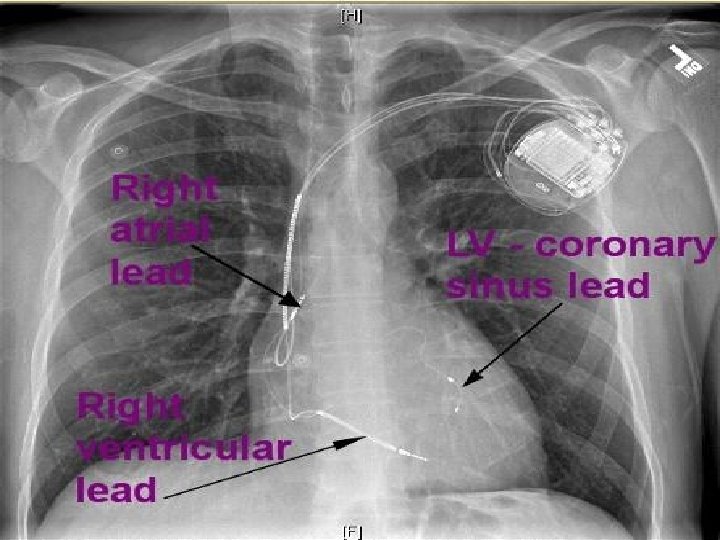

RATIONALE FOR CRT ‘PRESENCE OF BUNDLE BRANCH BLOCK CAN WORSEN HF DUE TO SYSTOLIC DYSFUNCTION BY CAUSING VENTRICULAR DYSSYNCHRONY, THEREBY INDUCING REGIONAL LOADING DISPARITIES AND REDUCING THE EFFICIENCY OF CONTRACTION. A VARIETY OF HEMODYNAMIC BENEFITS FOLLOW THE CORRECTION OF DYSSYNCHRONY WITH CRT. ’

CURRENT GUIDELINES FOR CRT • WITH LVEF <35% NICE, ESC AND ACC GUIDELINES RECOMMEND: • • CRT-D FOR NYHA CLASS 1 TO 3 PATIENTS WITH QRSD >150 MSEC CRT-D FOR CLASS 2 AND 3 PATIENTS WITH LBBB AND QRSD 130 -149 MSEC STAND ALONE CRT-P IN NYHA CLASS 4 PATIENTS WITH ECG CRITERIA AS ABOVE ROLE OF ECHO – DURING WORKUP LIMITED TO LVEF ASSESSMENT. SOME ROLE OF ECHO IN INTRAVENTRICULAR DYSSYNCHRONY ASSESSMENT IN LBBB WITHQRSD 120 -130 MSEC POST IMPLANT – ECHO HAS ROLE IN CRT OPTIMISATION